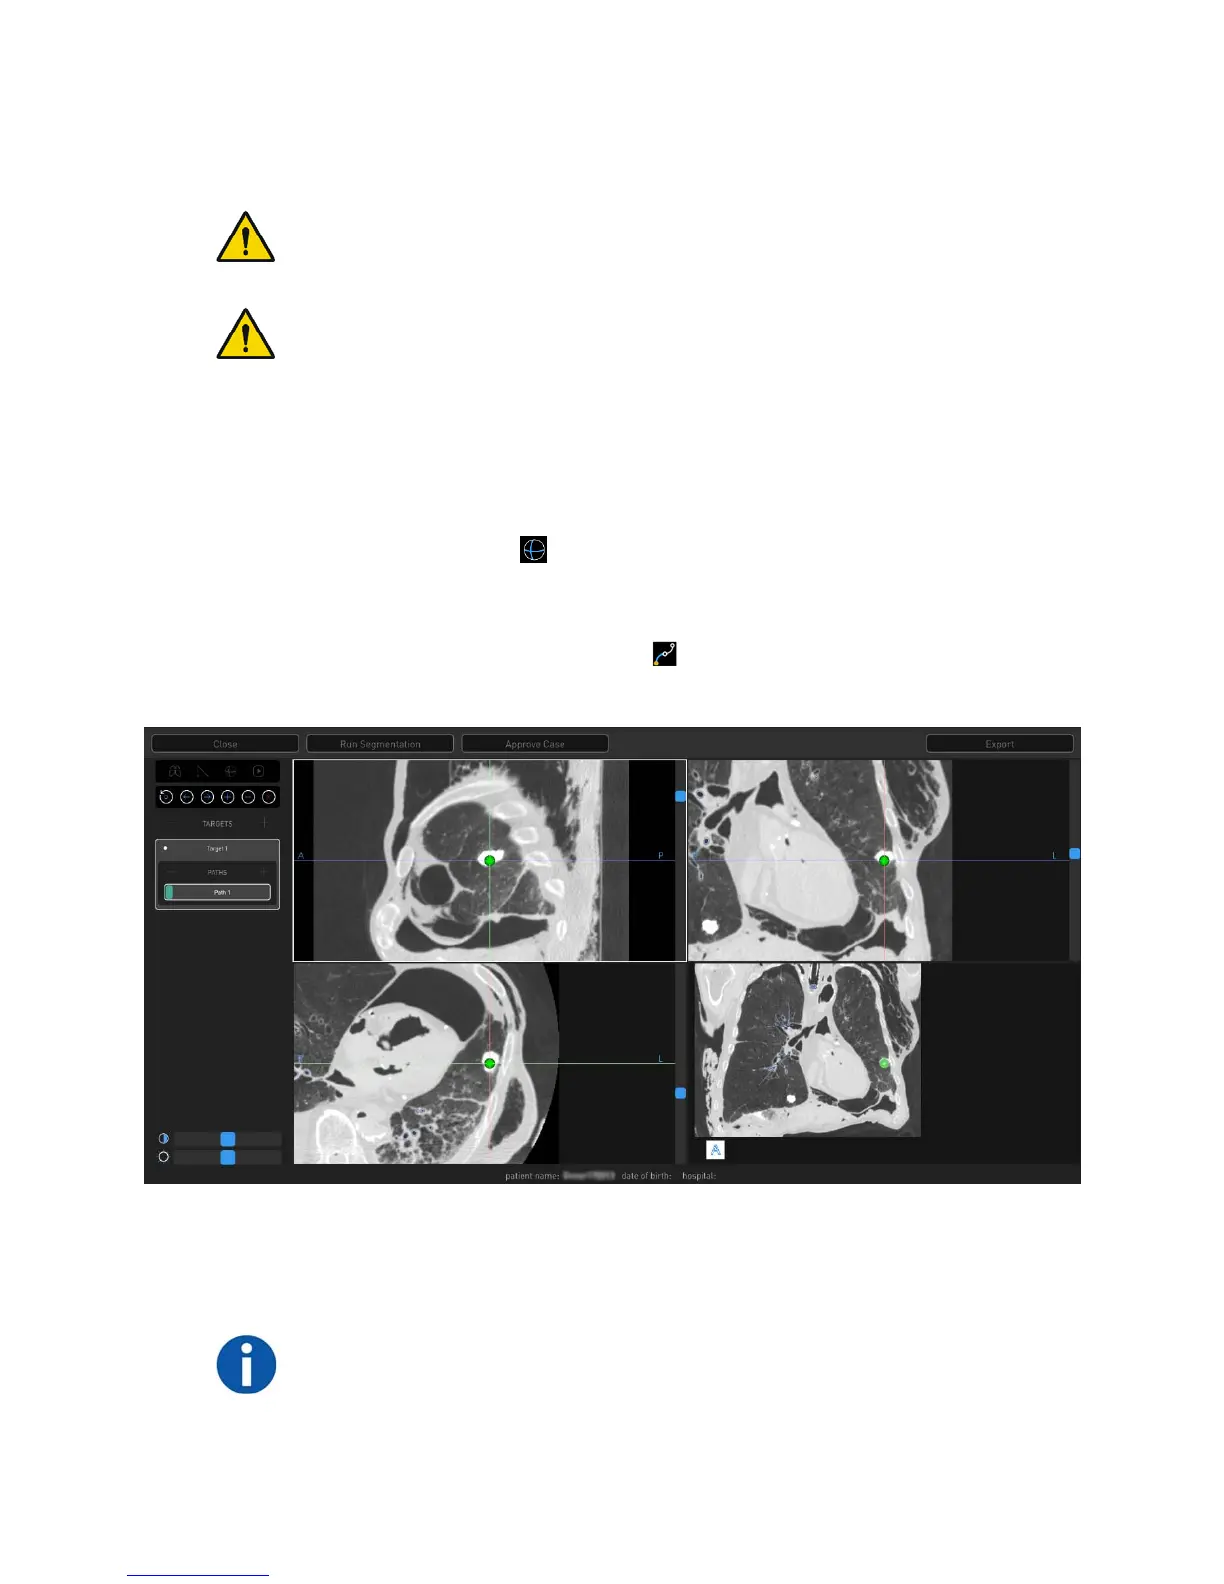

1. Place crosshairs over a region of interest in any of the CT views and click or

tap + next to Targets to create a new target. A new target and new path

appear automatically.

a. The target shape is based on the anatomy of region selected. Click or tap

the Sphere icon to change the target shape to a sphere. Right-click

and drag to adjust the sphere target size. Click or tap the Sphere icon

again to return to original target shape.

2. Click or tap the Manual Path icon if the target is beyond the default path

created during segmentation view or to create a manual path.

3. Insert drop points to create a manual path in the Segmentation view (lower-

right image viewer). Paths start at the nodule by default and work back

towards the main airway.

NOTE: Points can only be placed in the Segmentation view (lower-right image

viewer). This can be done in the small image viewer (as shown in the previous

image) or in full-screen mode. Full-screen mode is accessed by double-clicking